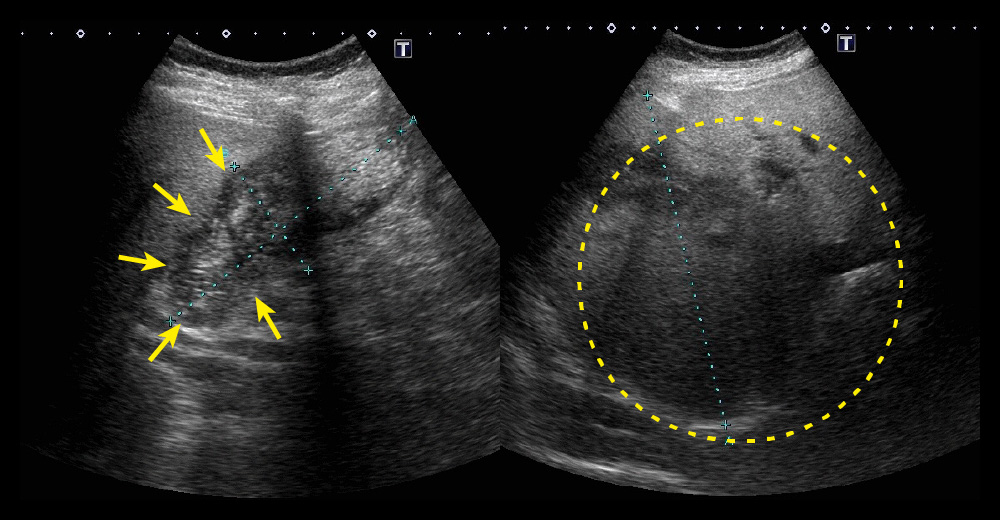

造影CT動脈相/造影CT動脈相*水平断|胆嚢底部に造影効果を伴う腫瘤と膵鉤部~下大静脈周囲リンパ節が一塊となって腫脹

造影CT動脈相/造影CT動脈相*水平断

胆嚢底部に造影効果を伴う腫瘤と膵鉤部~下大静脈周囲リンパ節が一塊となって腫脹

造影CT動脈相/造影CT動脈相*冠状断